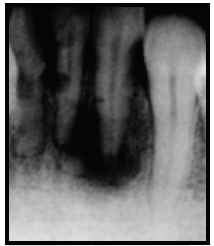

Analise a figura a seguir:

Enunciado 1407242-1

Radiograficamente, pode-se visualizar: